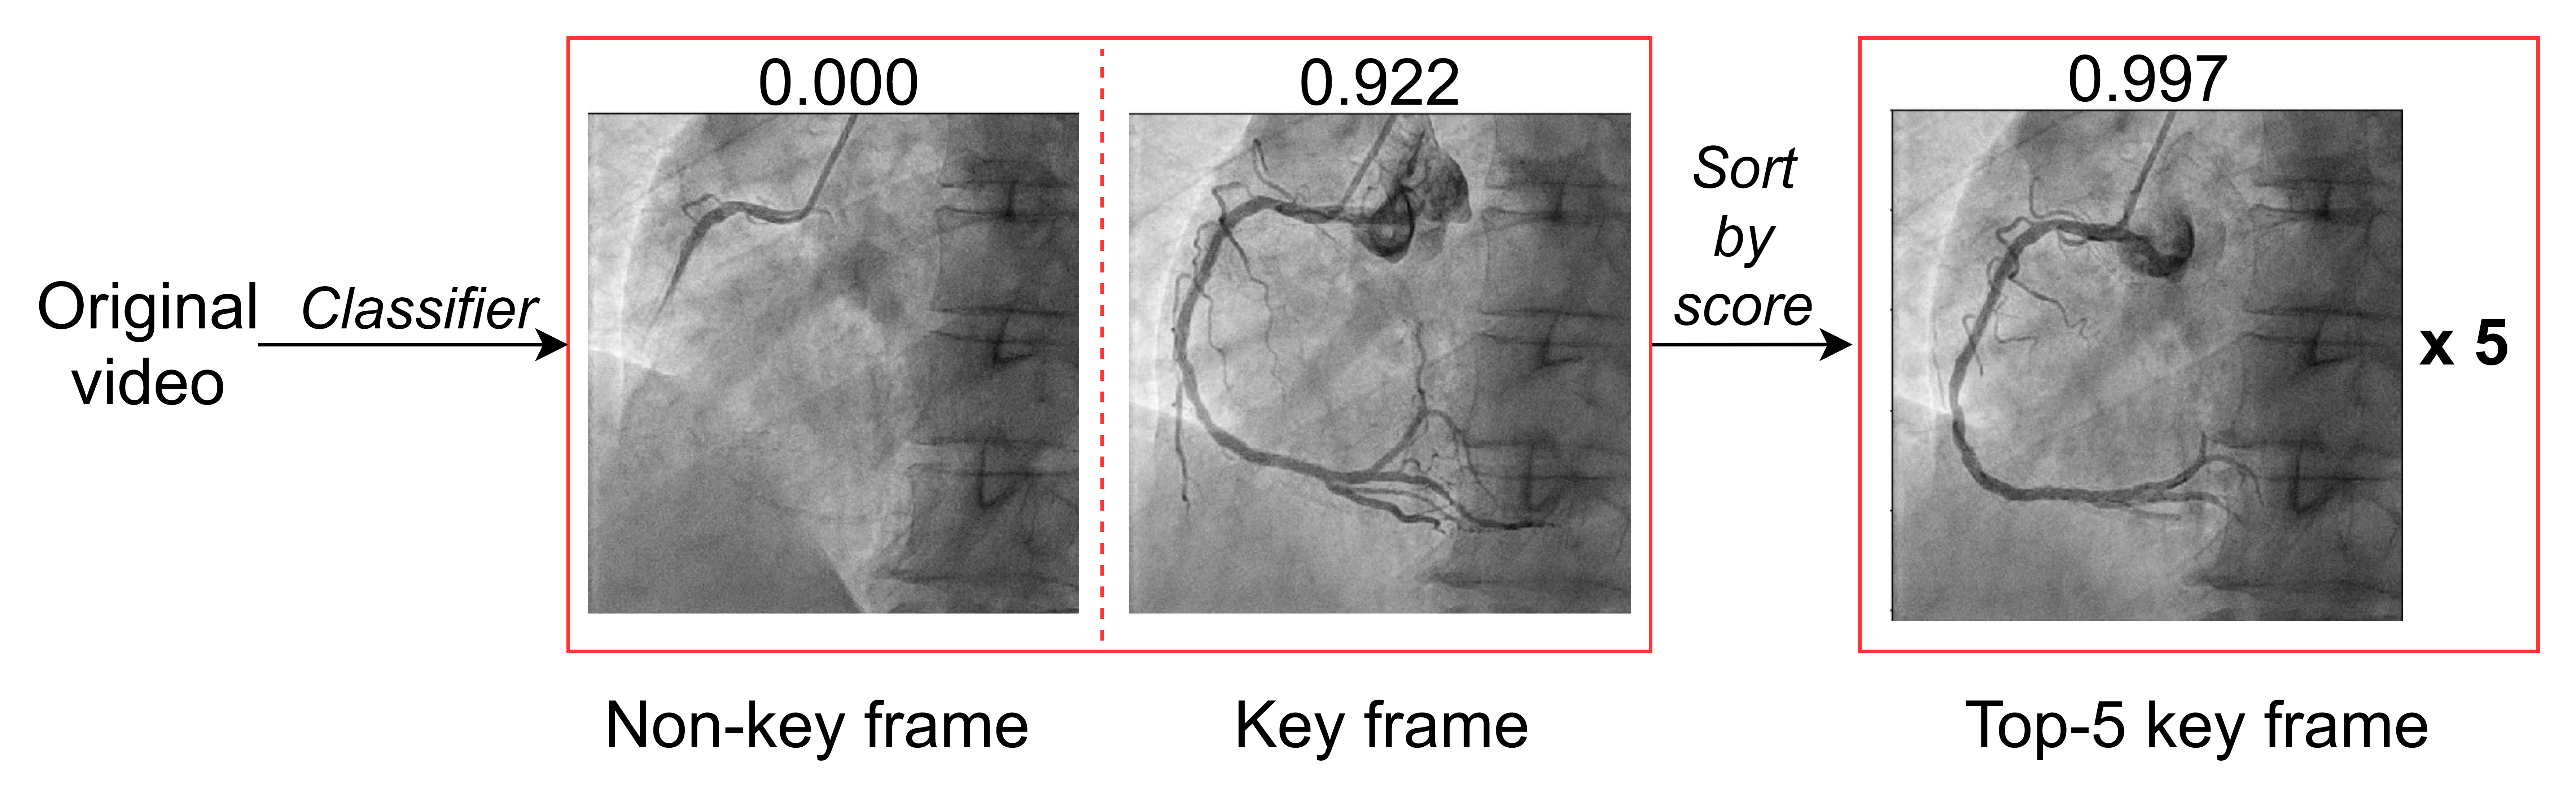

Figure 1: Schematics of methodology. (A) Workflow of the proposed angiography analysis pipeline with three main stages: extraction of key frames from video, vessel segmentation of the selected frames, and stenosis measurement through calculating vessel width, giving stenosis location and severity. (B) Key frame extraction process, showing machine prediction scores, left: two frames from the same video, one non-key (score: 0.000) and one key (score: 0.922), right: a top-5 key frame. (C) Illustration of labeled frames. (a) key frame. (b) vessel not fully formed. (c) contrast agent starts fading. (d) vessel has shifted out. (D) A key frame with corresponding segmentation label (the vessel region between the red arrows is the desired segment for segmentation). (E) Proposed stenosis measurement algorithm. Vessel width along the centerline is plotted to locate the minimum. Note that orange arrow in (c) points to the position of the most severe stenosis.

III-B Key Frame Extraction

Key frame extraction was implemented to select high-quality frames displaying complete vessel shapes for further analysis. We employed a two-phase algorithm for the training of key frame classification models (Fig. 1B). We first trained a base model on resized 64x64 images using manually generated ground truth labels of 6533 non-key and 2198 key frames. The set of criteria for key frames consists of high vessel clarity, a clear vessel edge, and visibility of the proximal, mid and distal RCA i.e. the contrast agent has reached the crux where the RCA divides into the posterior descending and acute marginal arteries (Fig. 1C). Key frames were labeled by student research assistants (C.Z., T.V.D., H.K.) trained and supervised by an interventional cardiologist (J.Y.) and postdoctoral researcher (K.L.).

Given a single image for prediction, the model generated a score indicating the frame quality (0 - low, 1 - high). Our algorithm then selected 5 frames with the highest scores from each video sequence. In addition to a typical per-frame accuracy metric, we introduced another metric calculating the percentage of true key frames out of the best 5 (“Top-5”) output frames of each video sequence (hereafter referred to as the “Top-5 Precision”).